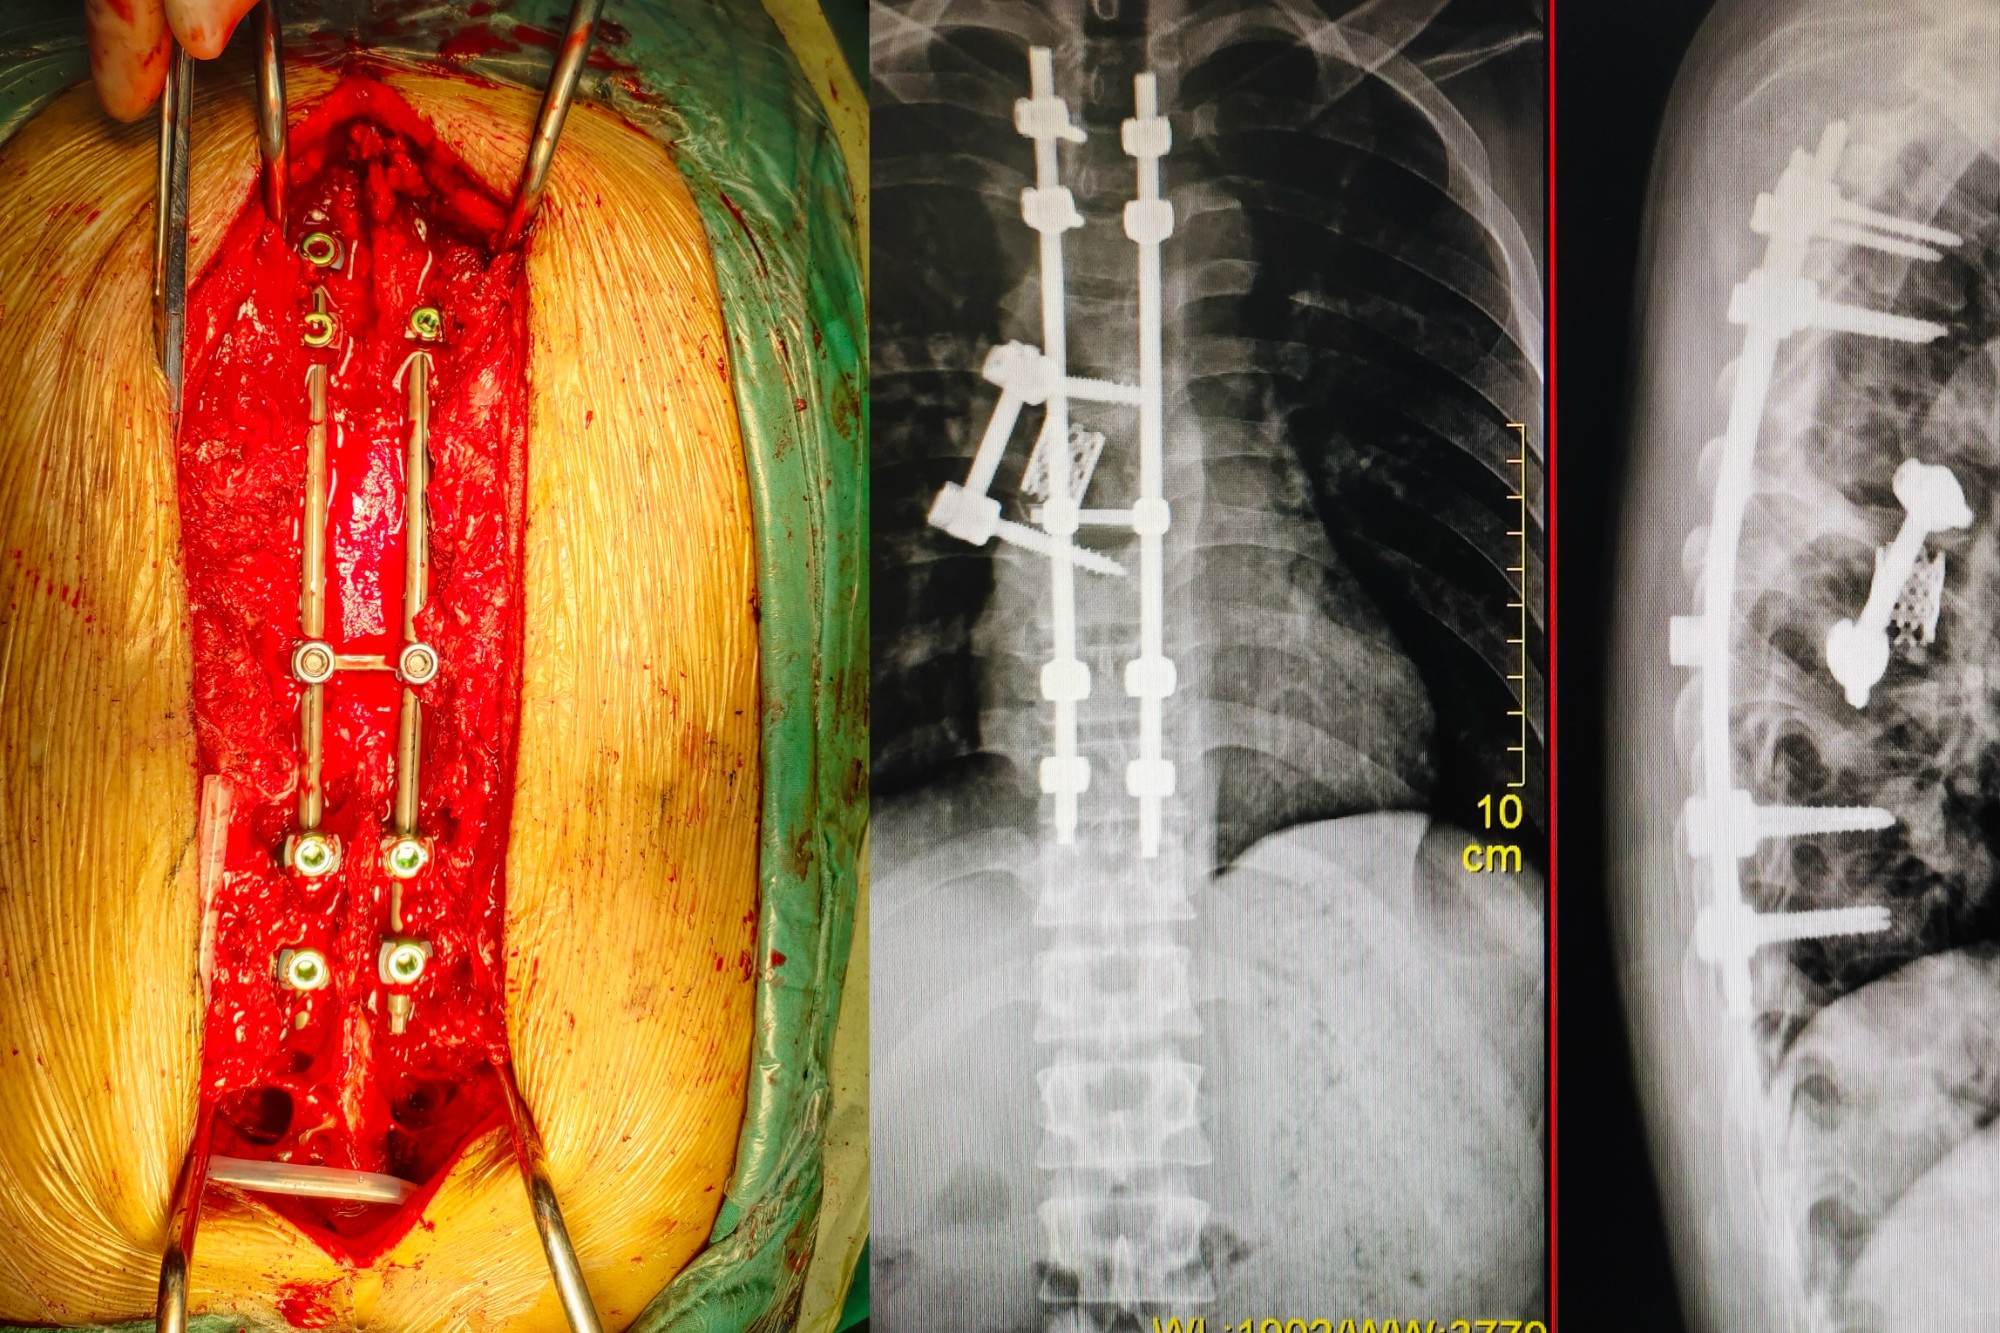

4、脊柱专科:重点开展脊柱骨折减压椎弓根螺钉内固定术,微创椎体成形术,椎间孔镜下椎间盘摘除术,椎间融合术,射频消融术等,同时也开展臭氧治疗各种颈肩腰腿痛,椎管狭窄症,椎体滑脱、脊椎肿瘤及结核的治疗。

脊柱骨折减压椎弓根螺钉内固定术